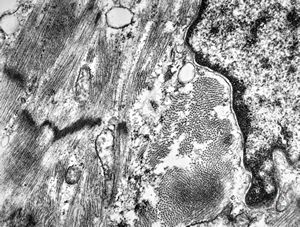

M,47y. | hypertrophic cardiomyopathy - left ventricle